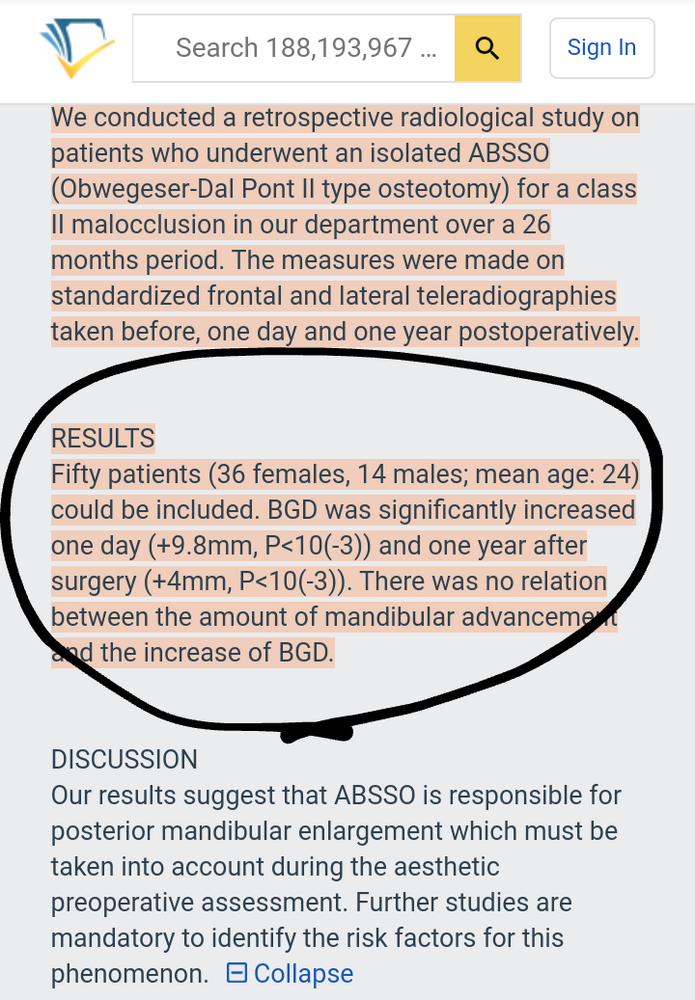

https://www.semanticscholar.org/pap...ahon/7ba8b84eeef2c292ef09a21455a049333d5559b7

Increase of 14 mm- fuckin LifeFuel

Also mandible looks much more squarer

If you get for example super bimax and get 11mm and after you get ABSSO (cause this osteotomy is ofter performed after bimax) and you will get~14 mm. You get fuckin 25 mm of your bone!!! Ewentually you can get after some jaw angle implant for further 10-12mm. Fuckin LifeFuel for narrowmandiblecels!